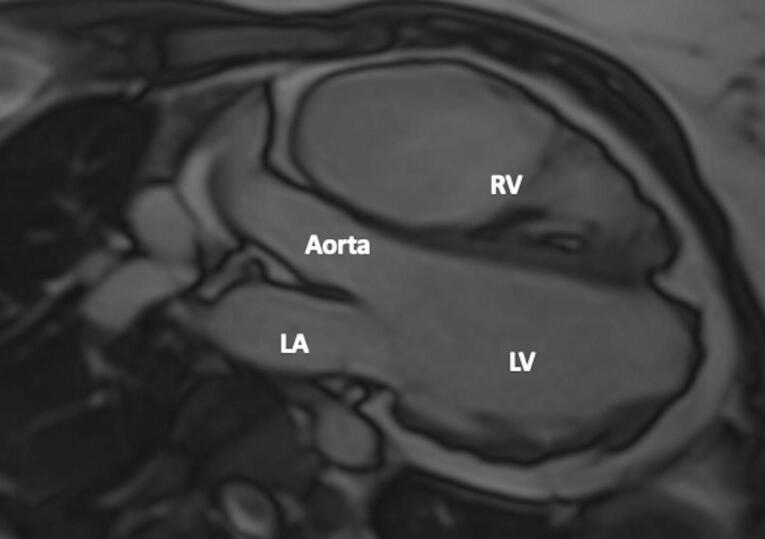

Herein we present a case of a right ventricular (RV) thrombus in a patient with arrhythmogenic cardiomyopathy (ACM). The 24-year old female patient was diagnosed with ACM after echocardiography, genetic test and cardiac magnetic resonance imaging. Interestingly, at echocardiography, an unusal thrombus formation was detected at RV lateral wall. Also, CMR confirmed the thrombus and oral anticoagulant therapy was started. During the patient's follow-ups, it was observed that the imaging consistent with the reported thrombus disappeared after effective anticoagulant treatment. After the diagnosis was confirmed with genetic tests, an implantable cardioverter-defibrillator (ICD) was implanted in the patient with a high sudden cardiac death (SCD) risk score. Even in arrhythmogenic right ventricular cardiomyopathy patients thrombi are rarely reported. However, the development of imaging techniques may enable more frequent detection and effective treatment of thrombi in these patients.